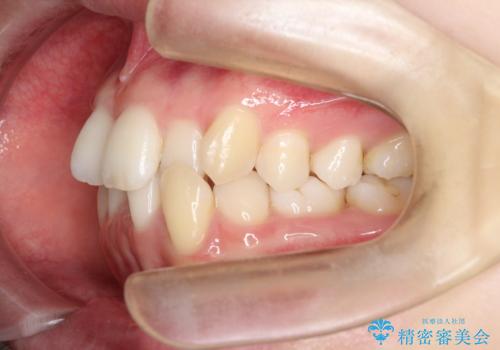

【インビザライン】 前歯の反対咬合を治したい

左下5番は先天性欠損のため乳歯は抜歯しインプラントにて欠損補綴しています。